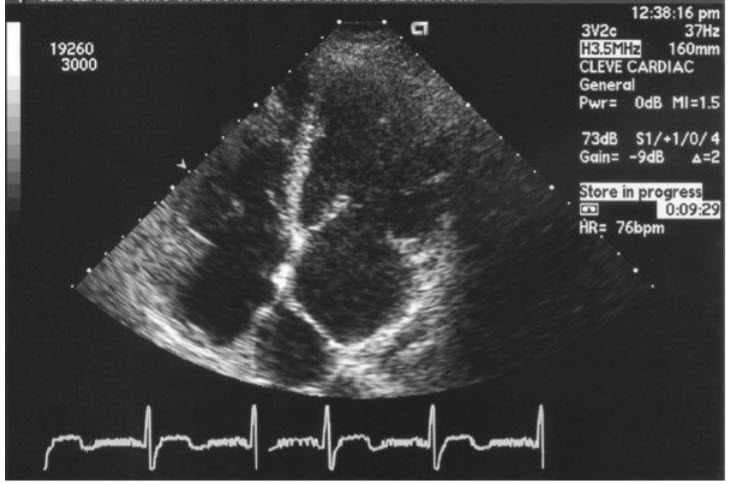

Match the following congenital cardiac disorder

Subaortic valve stenosis

with the characteristic transthoracic echocardiogram (TTE) finding in figures below:

a.

b.

c.

d.

e.